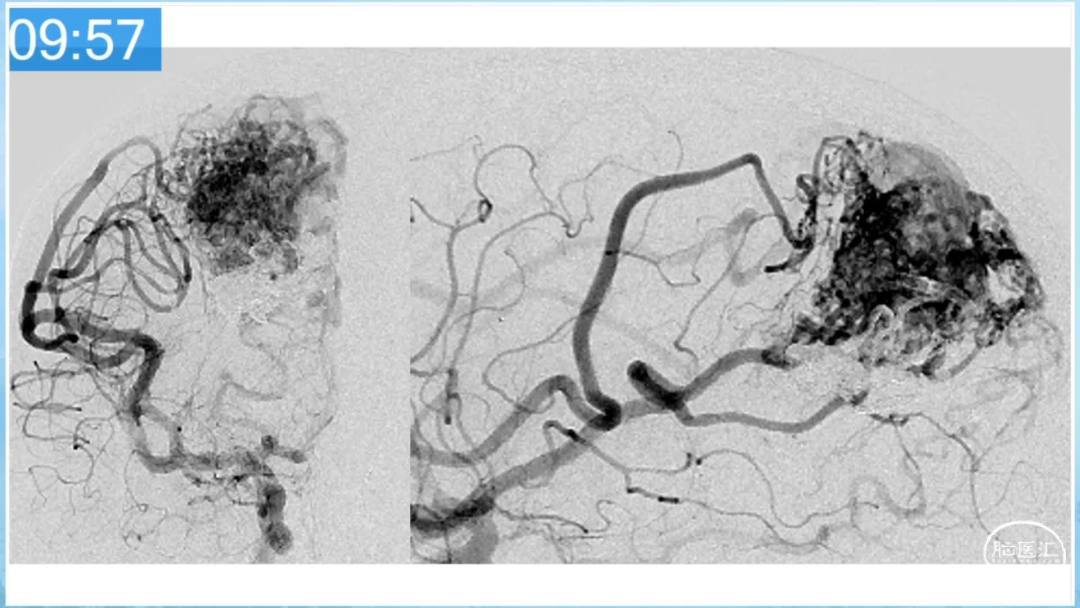

合理的复合平台下的综合治疗,针对每一个病变对应不同方法安全性分析,不预设、不排斥,每种技术发挥到最佳,互相保障。

本期为大家特别分享:空军军医大学唐都医院邓剑平教授的精彩会议内容《颅内动静脉畸形的复合手术治疗》,欢迎大家阅读和分享!